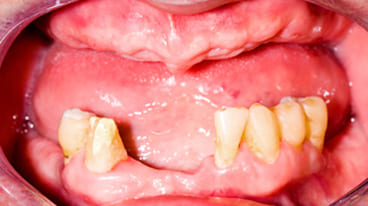

悪化させると歯が抜け落ちる

歯周病は、歯周病菌によって顎の骨が溶かされる病気で、進行すると歯ぐきの炎症、出血、口臭、膿などが見られ、最終的には歯が抜けてしまうこともあります。

進行度3

重度歯周病

(危険度★★★★★)

重度の歯周炎になると、歯がグラグラして、歯と接している歯茎がさらに腫れ、化膿が進みます。歯と歯の間が広がり、歯茎が下がって、歯が長く見えます。この段階の治療法は再生療法を用いて歯周組織の再生をはかるかことが多いです。しかし、ここまで進行すると抜歯になる可能性が高くなります。